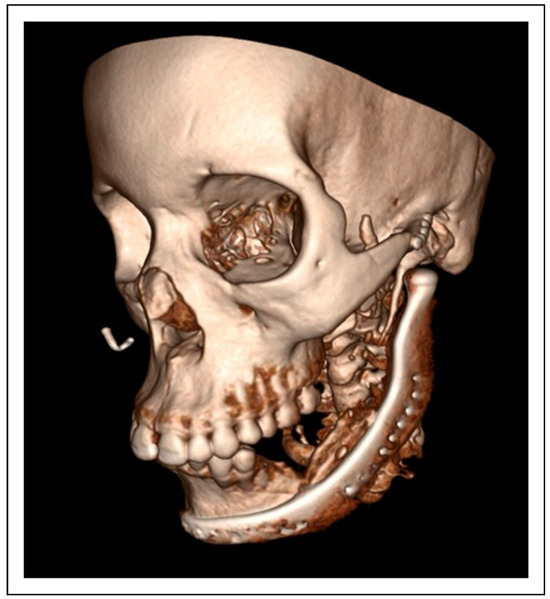

Bilateral TMJ Replacement With Complete Replacement of the Mandible, Patient 8